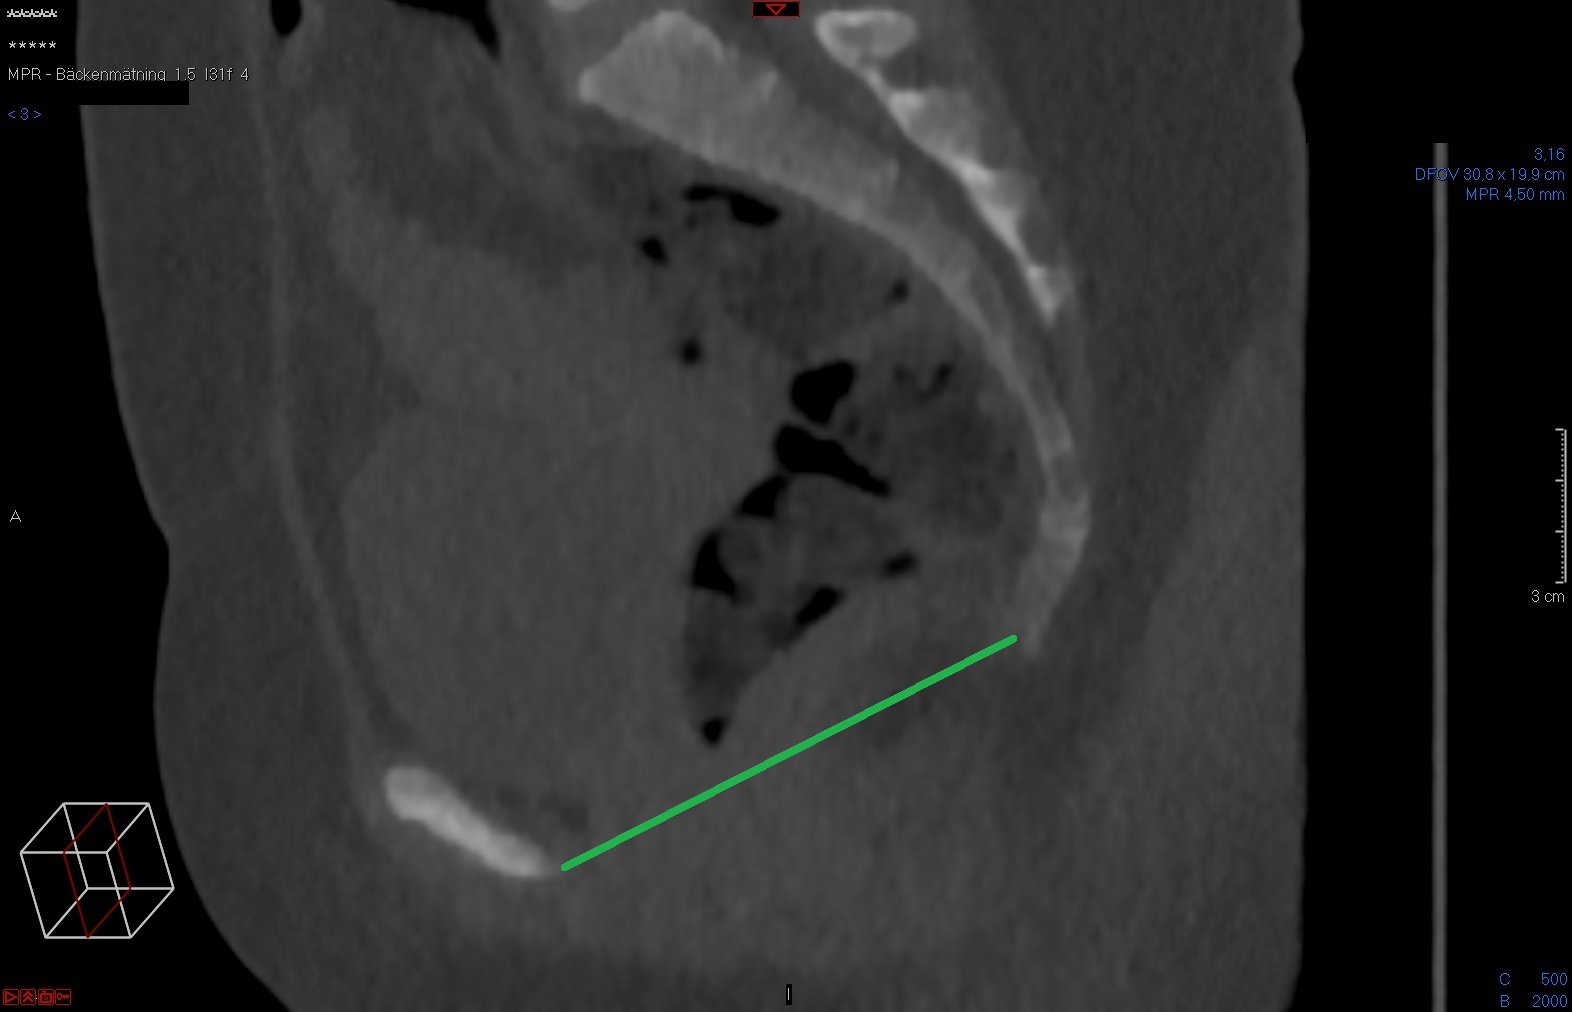

Tunna snitt-serien axialt i Power Viewern ("MPR"), snittjocklek 7-10 mm, skelettfönster. Scrolla fram till symfysens mitt. Mät det kortaste avståndet mellan symfysens kaudala-dorsala omfång och coccyx första böjbara led.